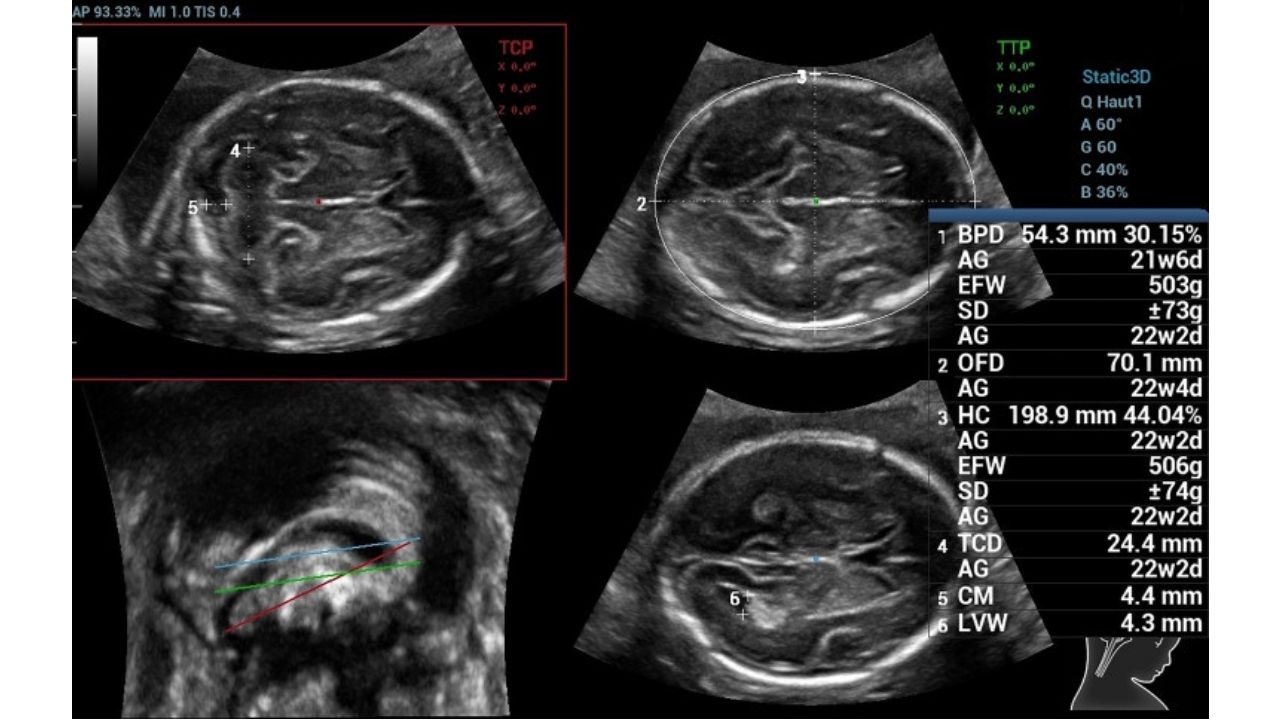

1. Khái niệm: 👩⚕️Theo Liên đoàn Sản Phụ khoa Quốc tế (The International Federation of Gynecology and Obstetrics – FIGO) 2021, thai chậm tăng trưởng (FGR) là việc thai nhi không đáp ứng được tiềm năng phát triển của nó do một hay nhiều yếu tố bệnh lý gây ra, thường gặp nhất là tình …